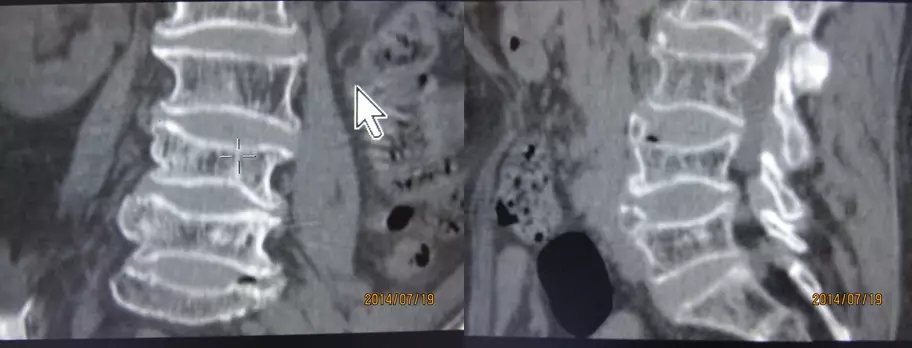

4.滑脱、峡部裂

腰椎前滑脱I度

椎弓峡部裂